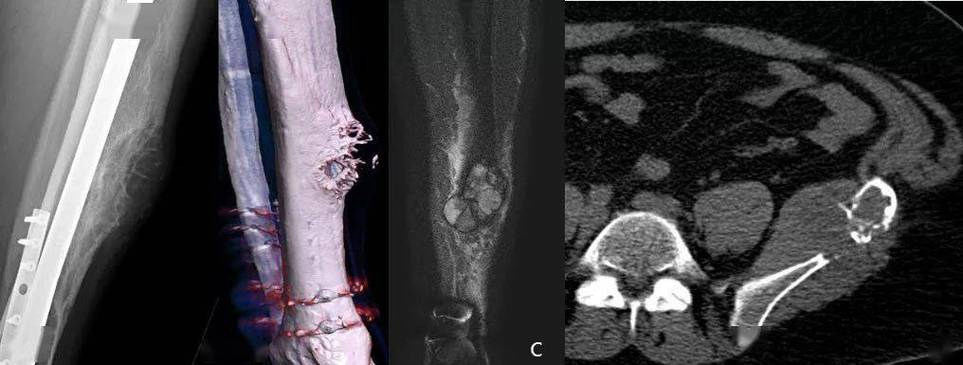

多发性骨髓瘤症状是什么

多发性骨髓瘤晚期症状较为复杂,主要包括以下方面1骨痛骨髓瘤细胞在骨髓中异常增殖,破坏骨骼结构,引发持续性骨痛疼痛常见于背部肋骨骨盆及腿部等部位,可能因活动加重,严重影响患者日常活动能力2贫血骨髓瘤细胞分泌的异常蛋白抑...